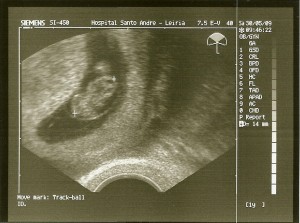

20090530_eco

Fizeram-me uma ecografia e parecia estar tudo bem com o embrião.

O meu maior desejo é que corra tudo bem!

O médico aconselhou-me a ter bastante cuidado e a fazer muito repouso!